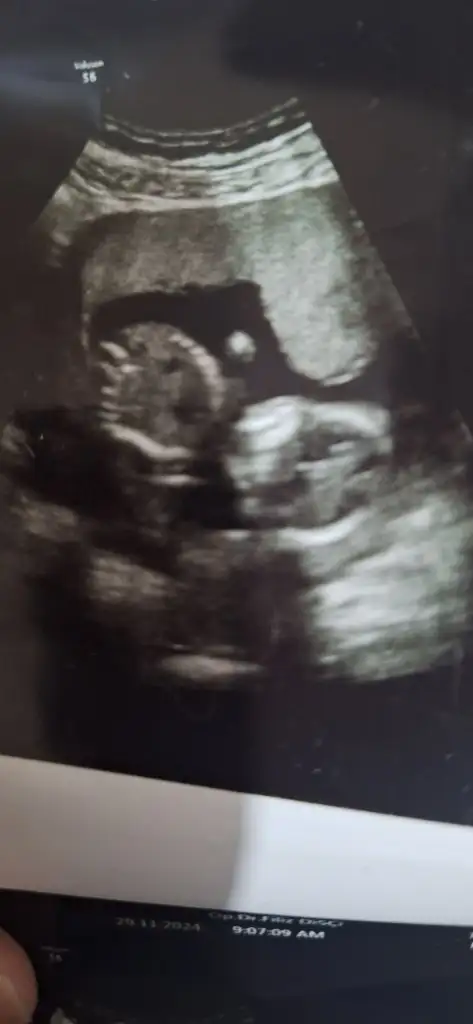

Bende de ilk ultrasondaki gibi erkek dediler 3 doktordaMerhabalar 16. Haftalık hamileyim doktor bir erkek dedi ama sonra kordon olabilir dedi bugun baska doktorda randevum vardi cinsiyet icin oda aynı seyi soyledi net degil kordon olabilir dedi ama bacak arasına bakıldıgında bence net gibi sizin fikirlerinizi merak ediyorum. Yorumlarınızı lutfen paylasir mısınız?

İki oğlum var birine hamileyim henüz. İkinci gebeliğimde cinsiyeti bizzat kendim gördüm ve Dr şaşırdı ultrasondaki doktor da şaşırdı sağlıkçı değilim deyince. Yani bence erkek o testise benziyor ortadaki ama pipi görmedikleri için net konuşmamışlardır.

Orda küçük bir çıkıntı gördüm doğruysa erkektir ya da kordonsa kız zatenAnlıyorsaniz benimkine de bakarmisiniz aceba rica etsem

Bazen kız bebek organı böyle dolgun ola biliyor doktor onun için kesin söylememiş ola bilir.Merhabalar 16. Haftalık hamileyim doktor bir erkek dedi ama sonra kordon olabilir dedi bugun baska doktorda randevum vardi cinsiyet icin oda aynı seyi soyledi net degil kordon olabilir dedi ama bacak arasına bakıldıgında bence net gibi sizin fikirlerinizi merak ediyorum. Yorumlarınızı lutfen paylasir mısınız?

Anlıyorsaniz benimkinede bakar mısınız size zahmetevet testise benziyor ama ortasında pipi de olmalı bence de net değil.